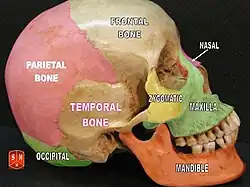

A caixa craniana é formada pelos seguintes ossos:

Osso temporal (par)

Osso temporal (par) -

Osso parietal (par)

Osso parietal (par)